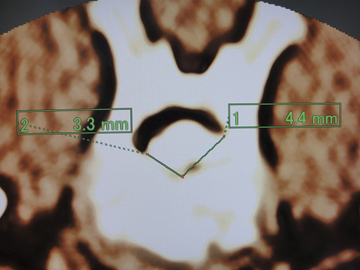

三次元CT検査は,手術計画を立てるにあたり,脊柱管内に逸脱した変性椎間板物質の詳細な情報を得るのに最良の検査方法の一つである。矢状断像での頭尾側方向への変性椎間板物質拡散範囲(図1),横断像での変性椎間板物質の左右方向への逸脱割合(図2),脊柱管背側方向への変性椎間板物質拡散範囲(図3),変性椎間板物質最大逸脱部位における脊髄圧迫の程度(図4),仮想内視鏡像での逸脱変性椎間板物質の形状(図5〜7)など多くの情報が得られる。

![]() 図2 横断像での変性椎間板物質の左右方向への逸脱割合 |